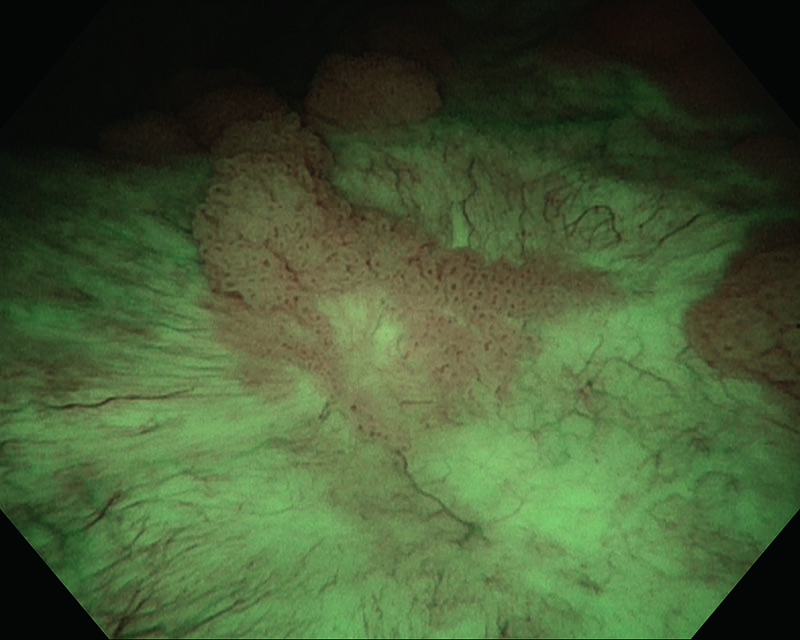

Tumor séssil papilar, mulher de 82 anos

Luz branca

NBI

Histologia UC, pTa de alto grau

Comentários

O uso da NBI nos permitiu aprimorar a visualização da região marginal do tumor. Além disso, a NBI nos permitiu identificar pequenos tumores ao redor que eram difíceis de identificar sob a luz branca